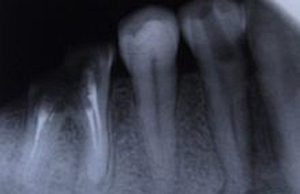

尖周炎癥

由于牙根的牙髓組織發(fā)炎,引起牙根尖組織病變,如根尖牙周膜腔增寬、根尖囊腫等病變均可在牙片上顯示出來(lái)。

尖周炎癥作牙片檢查的臨床意義有:

①了解病牙根管情況:如根管數(shù)目、粗細(xì)、彎曲度以及有無(wú)鈣化、有無(wú)內(nèi)吸收等情況。

②幫助確定病牙:如兩牙之間的瘺管插入牙膠尖作牙片檢查,可以顯示牙膠尖偏于某一牙齒。

③檢查治療情況:如牙片顯示根管充填是否到底或有無(wú)超填。